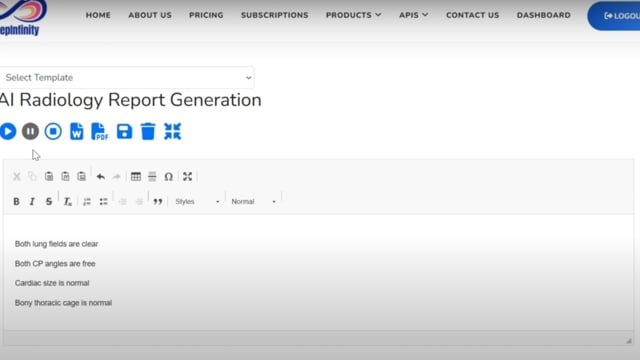

DeepInfinity.AI specializes in using advanced Generative AI and ML technologies to transform healthcare diagnostics and patient care. Our platform applies generative AI models for deep and accurate analysis of medical data, offering a range of predictive and diagnostic tools. These tools are designed to support healthcare professionals in making faster, more accurate diagnoses, thereby enhancing the overall quality of patient care. DeepInfinity.AI uses the advanced Generative AI technology to help Doctors, Hospitals and Diagnostic Centers & Labs etc.